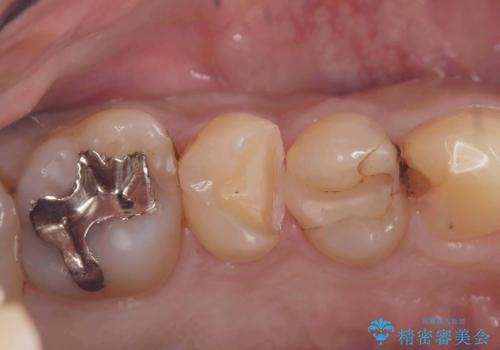

- CRの下が虫歯になっており歯が欠けている状態でした。古いCRと虫歯を除去しセラッミクインレーで治療しました。

CRが劣化し虫歯になり欠けている状態でした。歯を長持ちさせるために(再治療を減らす)セラッミクインレーで治療を行いました。